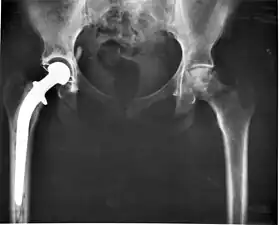

Hip replacement can be performed as a total replacement or a hemi (half) replacement. A total hip replacement consists of replacing both the acetabulum and the femoral head while hemiarthroplasty generally only replaces the femoral head. Hip replacement is currently the most common orthopaedic operation, though patient satisfaction short- and long-term varies widely.

Hip replacement surgery can be performed from three main directions, each with advantages and disadvantages The classical approach is the posterior, and requires dissection of the gluteus maximus and other large muscles of the back of the thigh to access the acetabulum. The anterior approach accesses the hip joint from the front, with less large muscle dissection but due to the proximity of the femoral artery, corresponding vein, and main nerve bundle for the leg lying just medial to the acetabulum the surgeon must exercise caution and maintain suitable landmarks. The lateral approach dissects smaller muscles than the posterior approach, but has similar navigation concerns as the anterior approach. Surgeon experience tends to determine the surgeon's preference, meaning that the surgeon will only rarely deviate from what method they were initially trained to use.